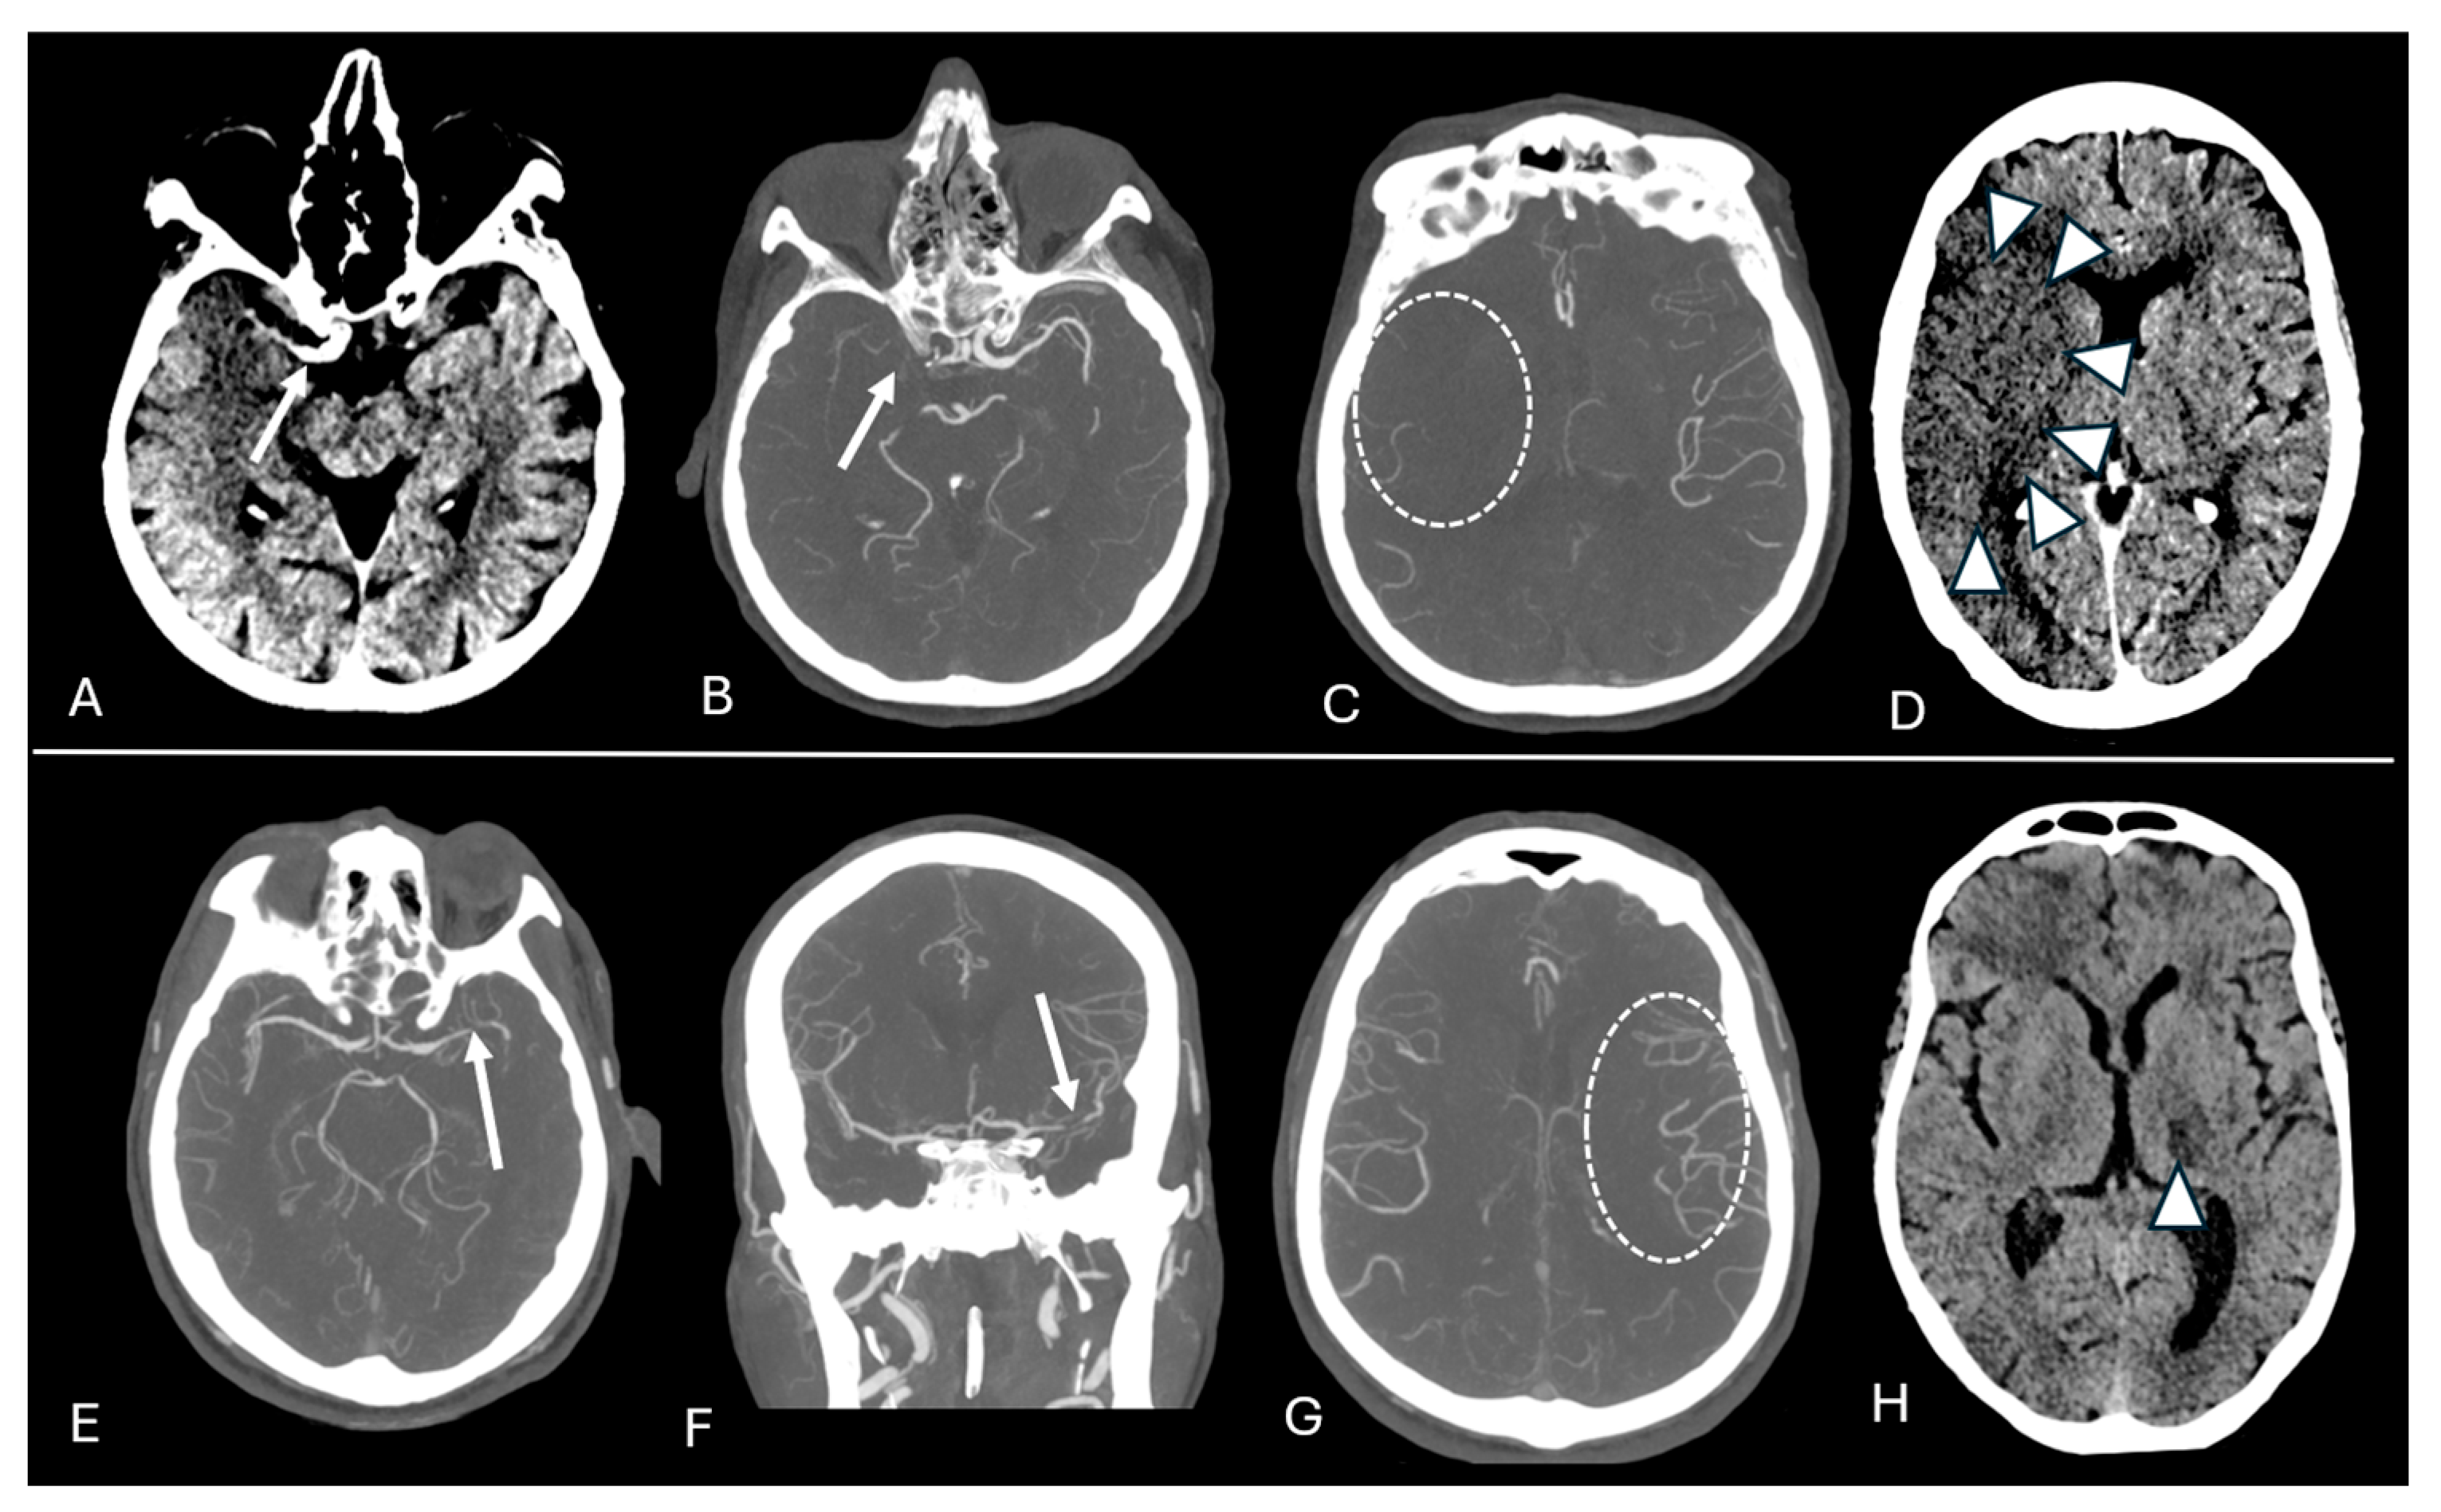

2.2. Imaging Protocol and Analyses